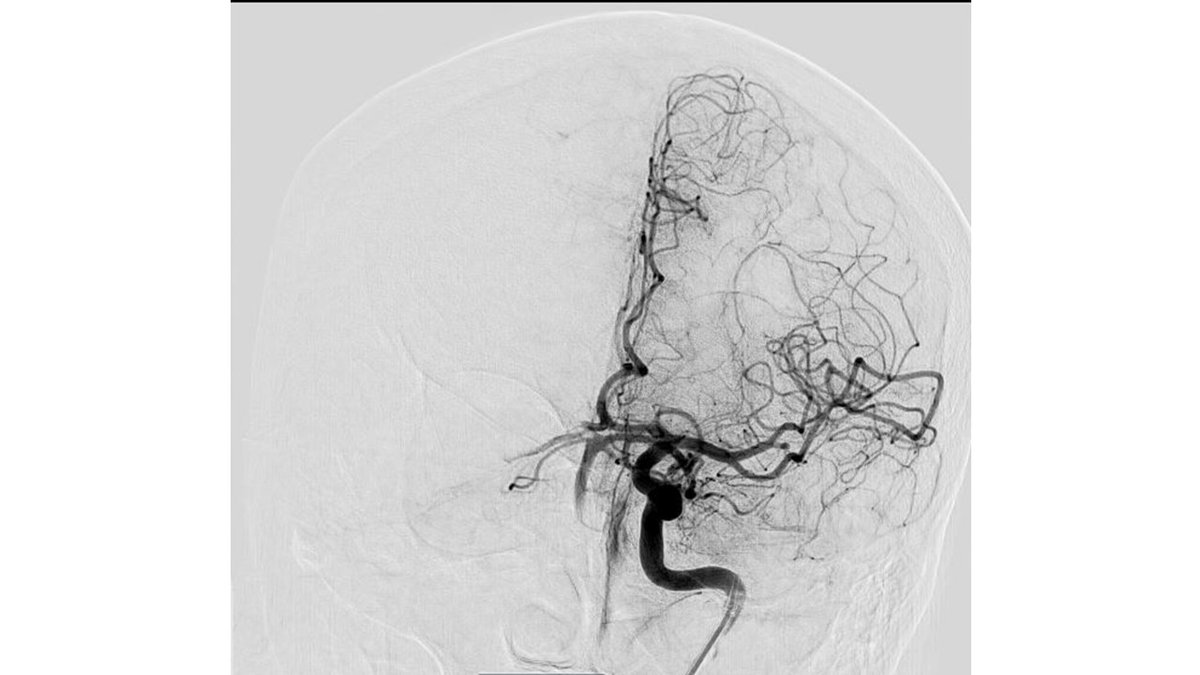

Thank you to Dr. Wei-Chiang, Chen out of #CMUH, #Taiwan🇹🇼, for sharing these great images from a first case using #RED43 in Left M2. Fantastic first pass and final TICI3 result. @PenNeuro